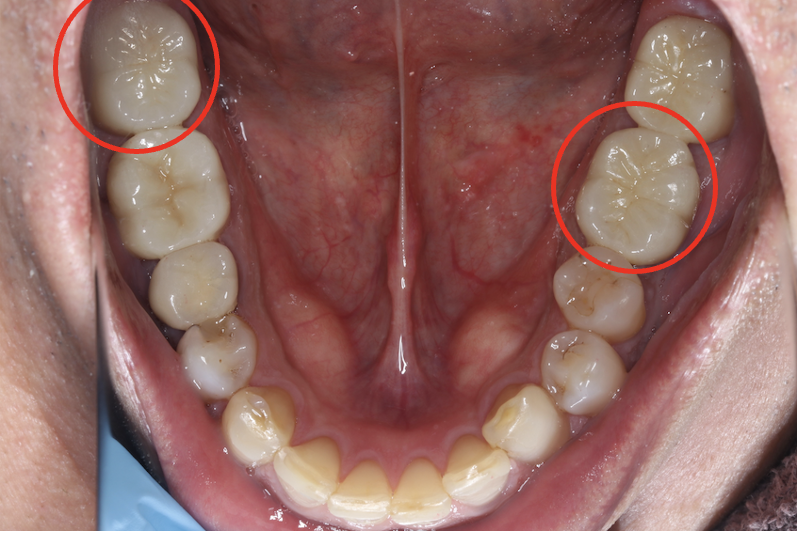

セラミック症例③

年齢30代女性

治療期間1ヶ月

治療内容セラミックインレー

治療箇所右下4番

治療費用100,000円